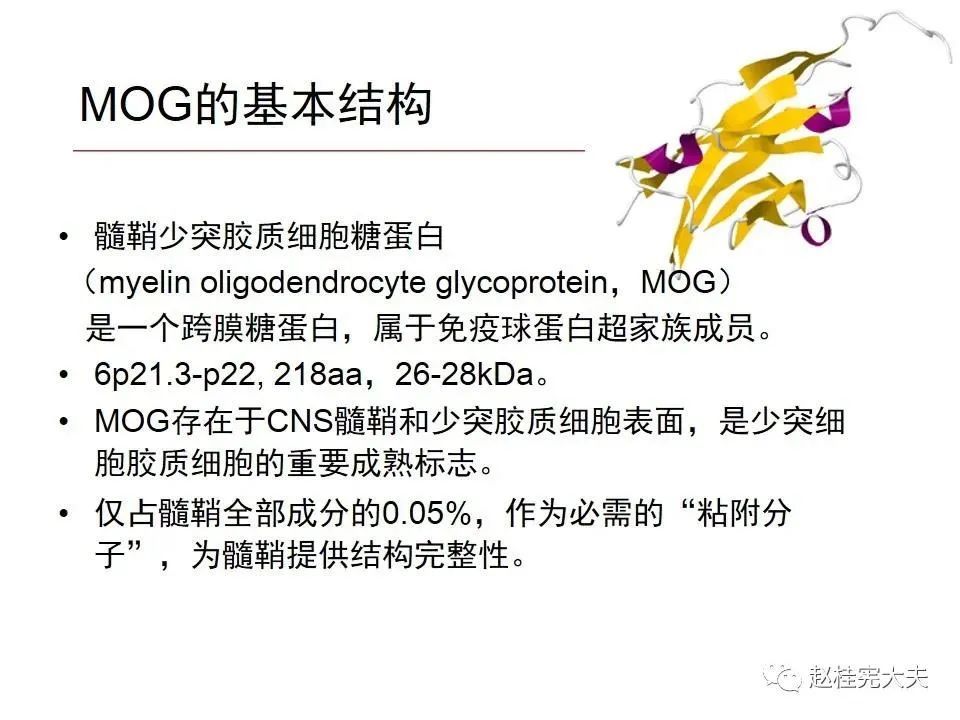

就是一种由MOG抗体介导的中枢神经系统自身免疫性疾病,目前被命名为MOG抗体相关性疾病,即MOGAD,在AQP4抗体未被发现,NMO/NMOSD还没有从MS分离出来时被诊断为MS,当NMO/NMOSD因AQP4抗体的发现从MS分离出后,它被诊断为NMO/NMOSD,在前几年,在一些AQP4抗体阴性的NMOSD患者中发现了MOG抗体阳性,MOG抗体相关性疾病才被认识,曾被命名为MOG脑脊髓炎,终于在2年前正式被命名为MOG抗体相关性疾病,当然,目前还有不少同道还将MOGAD诊断为NMOSD,按照其发病机制和分子靶部位,MOGAD和NMOSD是不同的,应该将其单独列为一个疾病去诊治。(个人意见,欢迎指正和讨论!)